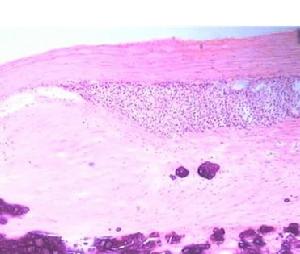

左腎囊腫是腎臟內出現大小不等的與外界不相通的囊性腫塊的總稱,常見的腎囊腫可分為成人型多囊腎、單純性腎囊腫和獲得性腎囊腫。單純性腎囊腫是臨床上最常見的一種囊腫性腎臟病,主要見於成人,發病率隨年齡而增加,50歲以上者約半數人至少有一個囊腫。囊腫可以是一側也可是二側,每個腎臟有一個或少數幾個囊腫。囊腫一般孤立呈球形,位於腎皮質淺表者可改變腎臟外形,也可位於皮質深層或髓質,直徑0.5~1㎝,也可3~8㎝,囊壁薄而透明,內含草黃色液體,較粘稠,如有過炎症,囊壁可增厚,纖維化甚至鈣化。囊腫與腎盂不相通,壁內襯以單層扁平上皮細胞。本病一般不出現症狀,常因其他目的或查體時無意中被發現。偶可出現血尿和局部疼痛、腎盞梗阻和繼發感染。症狀